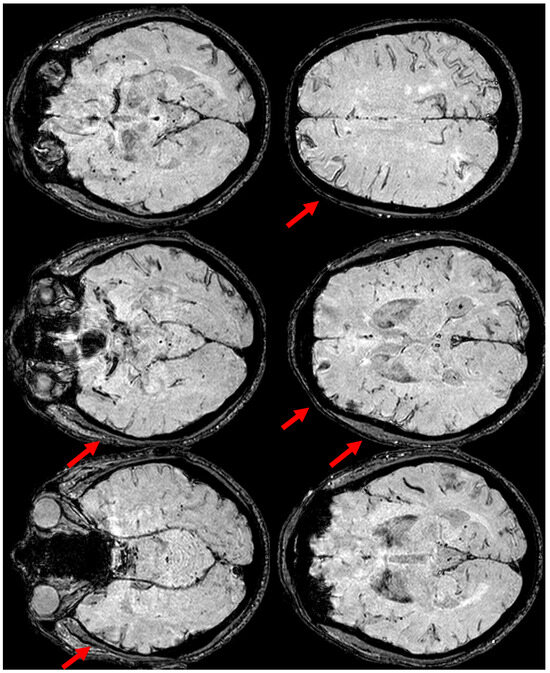

3. May 2014: CAA-Related Inflammation

5. February 2017: First Recurrent CAA-Related Inflammation

7. April 2018: Second Recurrent CAA-Related Inflammation

8. April 2018: Third Recurrent CAA-Related Inflammation